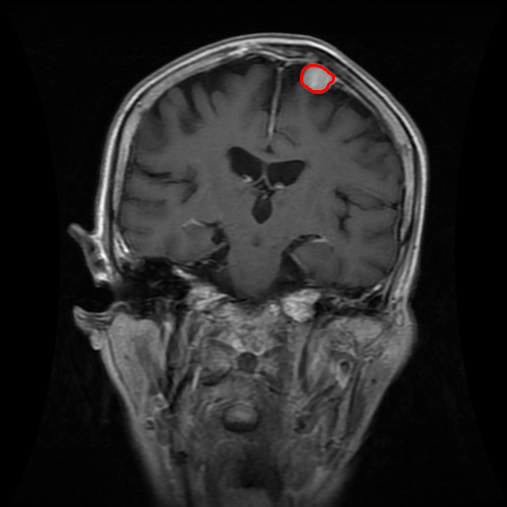

4.4 Comparison with cardic MR images for left ventricle segmentation

In this section, we continue to conduct experiments on cardiac MR images. However, we focus on the right ventricle, which is equally important as the left ventricle in cardiac MR diagnoses. In the near short-axis view, the left ventricle has a crescent shape, while the right ventricle is closer to circular. This does not imply that the right ventricle is easier to segment; in the MR images we use, the right ventricle often shows low-signal-intensity shadows, which may be caused by the imaging characteristics of certain tissues or fluids, leading to interference in segmentation. Moreover, there is a layer of myocardial tissue surrounding the right ventricle that overlaps with the boundary of the right ventricle, posing challenges for accurate identification.

Fig. 8 presents the segmentation results of the right ventricle from the DRLSE-ADMM [WALI2023109105], ABC model [WENG2021115633], RESLS [8765635], the RefLSM, and the ground truth. The results from the DRLSE-ADMM model in the 1st row reveal severe local minima due to low-signal-intensity shadows in the right ventricle. Additionally, both the ABC and RESLS models fail to correctly identify the right ventricle boundary because of the interference from surrounding myocardial tissue, as seen in the 1st and 3rd columns of Fig.8. In comparison, the proposed model gets more satisfactory segmentation results that are closer to the ground truth. Similarly, we evaluate the segmentation performance of all models by calculating the Dice and Precision values and drawing Fig. 9. This overlay plot presents the best, median and worst segmentation results, along with the overall range of outcomes that it is clear that the proposed model segments the right ventricle with greater accuracy than the other models and performs well in different images.